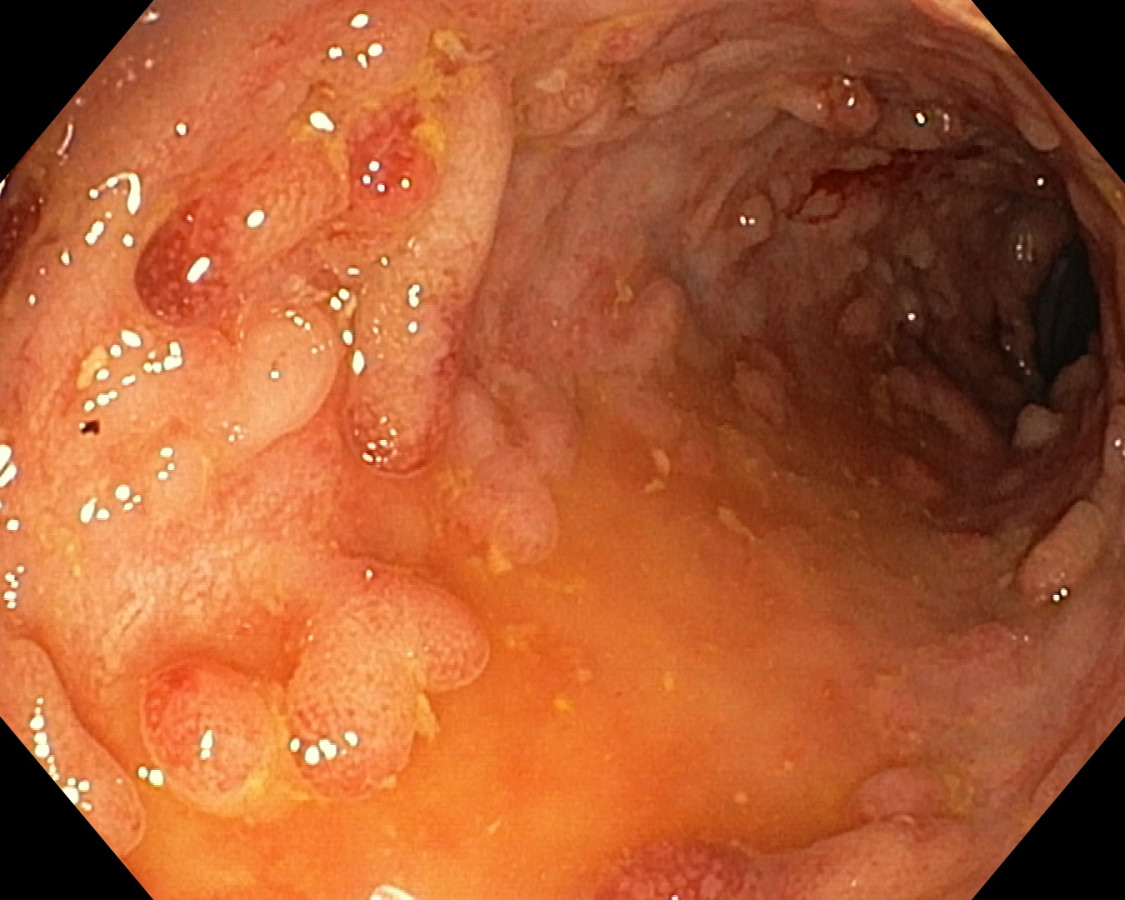

Polypóza u pacienta s ulceróznou kolitídou

Pacient s UC - dg. od r. 2009 ako pankolitída, od 4/2010 pri imunosupres. th. kompletná remisia ochorenia, už vtedy pseudopolypózne štádium, noncompliance, kontrola až pri relapse v r. 2017. Odvtedy +/- chodí na kontroly. 07/2023 relaps, systémové kortikosteroidy, ATB, s efektom - 9/2023 pankolonoskopia - pravostranne nález dobrý, ľavá strana síce bez aktivity ochorenia, aj histolog. remisia, ale polypózne št. hlavne v sigme - foto - dysplázia zachytená nebola. Bude ťažké odsledovať KRCA v tomto teréne. Dalo by sa uvažovať o chirurgickej liečbe ? Ďakujem.

U nemocných s UC je výskyt zánětlivé polypózy, kterou rozumíme přítomnost více než deseti zánětlivých polypů, relativně častý. Je odrazem těžce probíhající zánětu. Zánětlivé polypy nemají sami o sobě potenciál maligní degenerace a v tomto ohledu není potřeba je kontrolovat nebo odstraňovat. Mnohočetné zánětlivé polypy však znesnadňují průběh dispenzárních koloskopických prohlídek, protože významně omezují přehlednost po sliznici a detekci dysplastických změn. Druhý negativní dopad vícečetných zánětlivých polypů je u udržování aktivního zánětu a elevaci hodnot fekálního kalprotektinu. U nemocných s mnohočetnými zánětlivými polypy v rektu a rekto-sigmatu mohou být persistující tenesmy a intermitentní krvácení vyvolány právě jejich přítomností. V těchto případech je endoskopicky odstraňujeme.